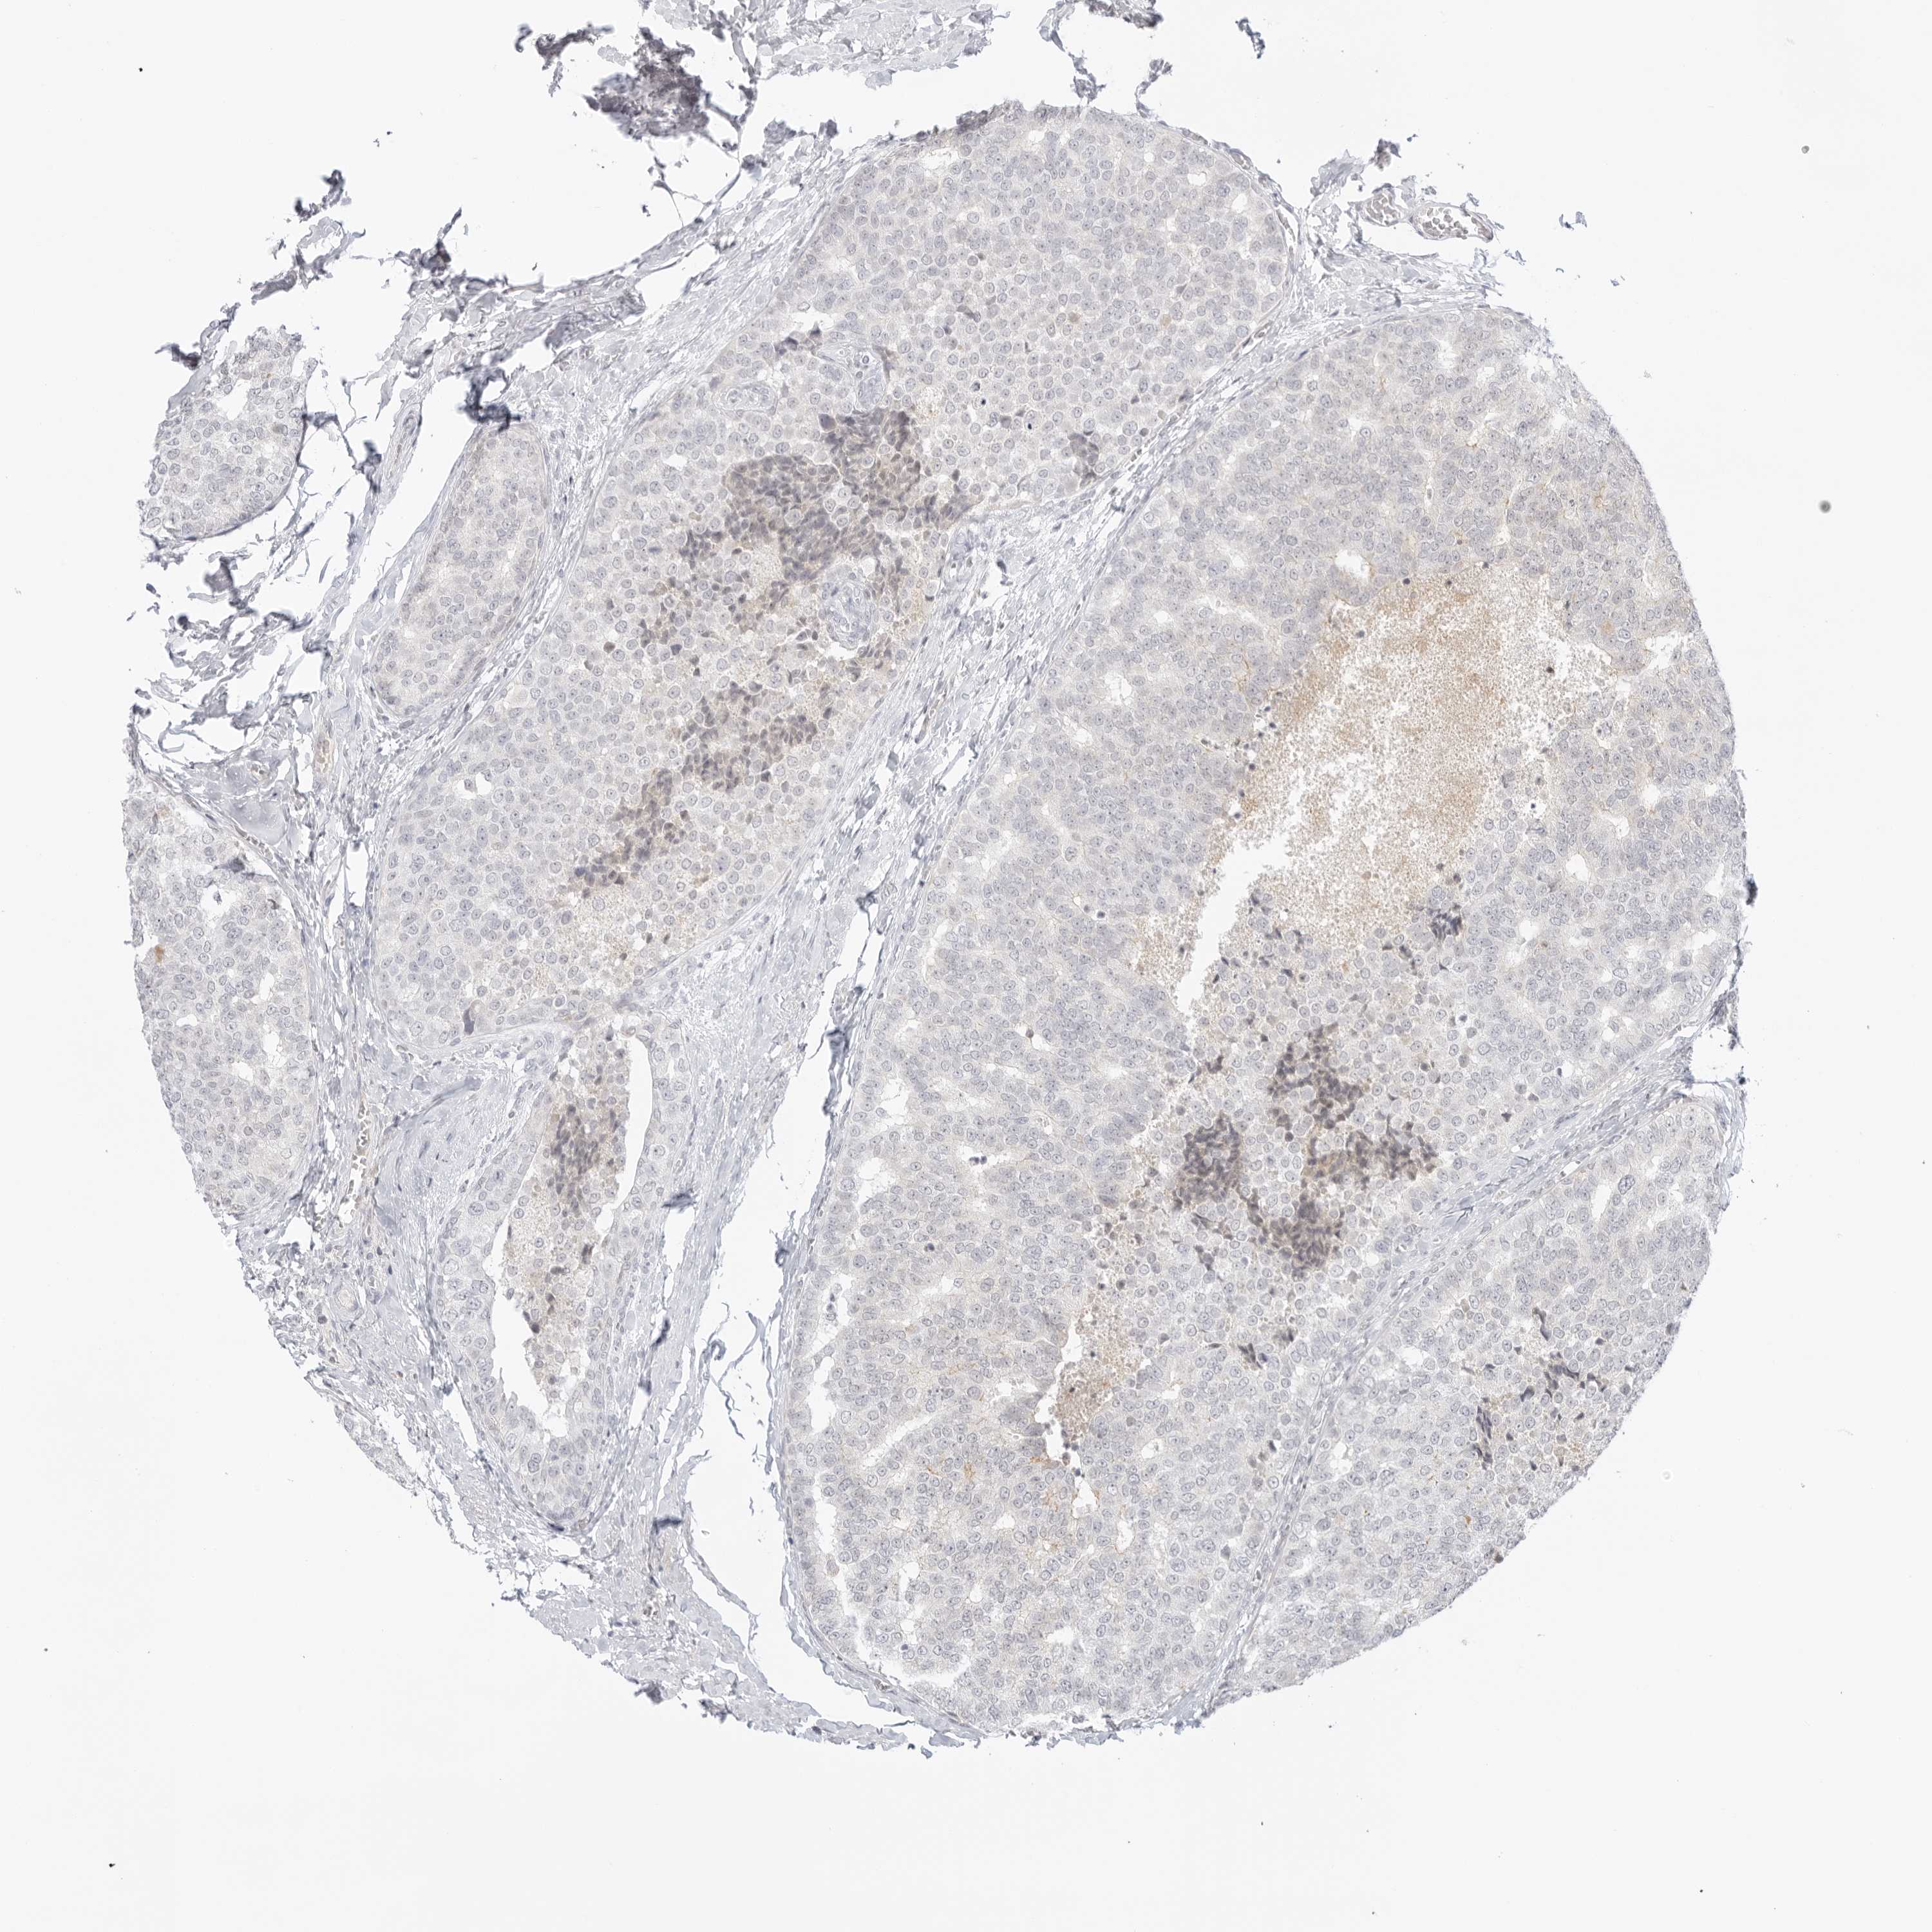

CANCER BREAST CANCER Show tissue menu

BRCA TCGA BRCA VALIDATION PROTEIN EXPRESSION